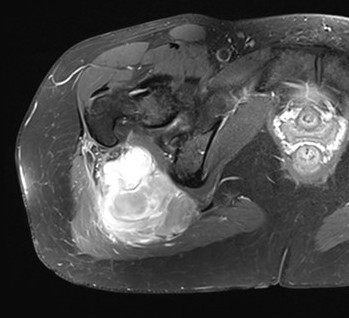

MRI

Heterogenous mass, low signal intensity T1, high signal intensity T2

- may have characteristic triple signal intensity

- area hyperintensity, isointensity and hypointensity

Buttock